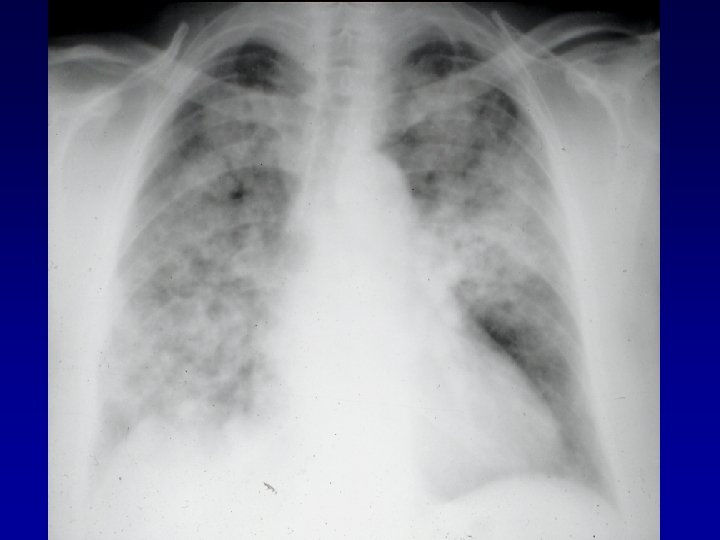

Radiologie: • Radiographies: – Poumons: • WG: Infiltrats interstitiels ou alvéolaires, parfois evanescents Nodules pouvant devenir cavitaires 34% des patients: infiltrats/nodules asymptomatiques • CSS: Infiltrats (surtout) evanescents chez 38 -70% Nodules: moins fréquents, moins tendance à cavitation Hémorragie alvéolaire: rare • PAM: Infiltrats alvéolointerstitiels 70%